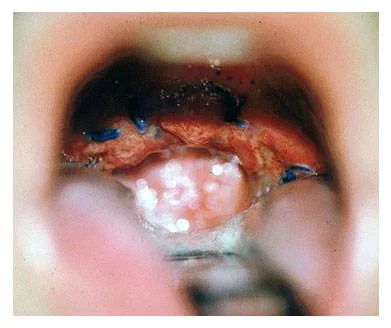

Essa cirurgia pode ser realizada de duas diferentes maneiras: sob anestesia geral, com duração aproximada de vinte a trinta minutos, quando é realizada junto à retirada das amígdalas. Quando o realizamos sem retirar as amígdalas, é um procedimento bem mais rápido e fácil, com duração aproximada de cinco a dez minutos, sob anestesia local.